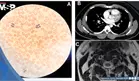

Dolor torácico pleurítico como presentación de hematoma intramural y disección de aorta ascendente